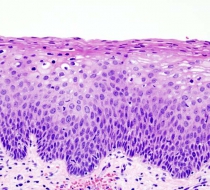

Tarihçeye bakacak olursak preinvaziv lezyonlar ilk kez 1900 yılında Cullen tarafından uterusda invaziv olmayan lezyonlara ithafen fullanılmıştır.Ardından Schaueristein (1908), Pronai (1909), ve Rubin (1910) süperfisial metaplastik epitelin yassı hücreli karsinomun erken evresi olduğunu ileri sürmüşlerdir. 1927 yılında Schiller preinvaziv neoplazi kavramını destekleyen bulgular sunmuş ve Broders 1932 yılında ilk kez karsinoma insitu (CIS) terimini kullanmıştır. 1940’larda ise Papanicolau eksfoliatif sitolojiyi gündeme getirmiş ve uterin ve servikal kanserlerin taramasında kullanılmasını önermiştir.1950’lerde de Amerikan kanser derneği servikal sitolojinin tarama amaçlı kullanılmasını desteklemiştir (1). Preinvaziv servikal hastalık kavramı ise 1947 yılında invaziv kanser görünümüne sahip ancak epitele nınırlı değişiklikleri tanımlamak için kullanılmıştır. Reagan ve arkadaşları 1956’da CIS ile normal epitel arasındaki histolojik ve sitolojik farklılıkları gösteren anormallikleri displazi olarak adlandırmış; hafif, orta ve şiddetli olmak üzere 3 gruba ayırmıştır. 1961 yılında 1. Uluslararası Eksfoliatif Sitoloji Kongresi’nde CIS teriminin epitelin tüm kalınlığının farklılaşmamış neoplastik hücreler tarafından oluşturulan lezyonlar için kullanılmasına karar verilmiştir. Displazi ve CIS’ın sürekli bir olayın farklı basamaklarını teşkil ettiğini düşünen Richart, 1967 yılında servikal intraepitelial neoplazi (CIN I, II, III ) terimini tanımlamıştır. Sonraki çalışmalar bu lezyonların tedavi edilmemeleri halinde servikal kansere yol açabileceğini gösterdi (1). 2001 Bethesda sisteminin sitolojik anormallikler için kullanılmaya başlamasi ile birlikte klinik terminolojimize serviks kanserine dönüşme potansiyeli olan lezyonları tanımlamak için, LSIL (Low (Düşük) dereceli skuamoz intraepiteliyal lezyon) ve HSIL (Yüksek dereceli skuamoz intraepiteliyal lezyon) terimleri girmiştir. Histolojik sınıflamada CIN1,düşük dereceli lezyonları CIN2,3 ise yüksek dereceli lezyonları içermektedir. Sitolojik LSIL’in histolojik CIN1’e ve sitolojik HSIL’in histolojik CIN 2,3’e eşit olmadığı da daima akılda tutulmalıdır (1). Bu derlemede servikal preinvaziv lezyonların tanımı, dünyada ve ülkemizde görülme sıklığı ve Amerikan servikal patoloji ve kolposkopi derneği tarafından önerilen yönetim algoritması özetlenecektir. Servikal Intraepitelyal Neoplazi Tanımı CIN Tanımı, Etiyolojisi, Histolojisi ve Sınıflaması: Anormal servikal lezyonlar ; epitelin alt 1/3’ünde sınırlı ise Servikal Intraepiteliyal Neoplazi I(CIN I) , alt 2/3’ünde ise CIN II, epitelin tamamına yakını tutulmuş ise CIN III, tamamını içeriyorsa Karsinoma İn Situ (CIS) olarak adlandırılır. Bütün lezyonlarda bazal membran sağlamdır. Fakat CIN’lerde invazyon potansiyeli her aşamada vardır. İnvaziv servikal kanserler genellikle uzun bir preinvaziv hastalık evresini izlerler. Mikroskopik olarak, invaziv karsinomlara ilerlemeden önce hücresel atipiden, değişen derecelerde servikal intraepitelyal neoplazilere (CIN) ilerleyen prekürsor lezyonlar spektrumu ile karakterizedir. Epidemiyolojik çalışmalar, CIN ve servikal kanser gelişimine katılan bir dizi risk faktörü belirlemiştir fakat günümüzde en önemlisi HPV olarak kabul edilmektedir (11). 10-15 yıllık uzun bir preinvazif döneme sahip olması, sitolojik tarama yöntemlerinin mevcudiyeti ve preinvazif lezyonların etkin şekilde tedavi edilebilmesi nedeniyle invazif serviks kanserinin önlenebilir bir kanser olduğu düşünülür. Nitekim serviks kanseri tüm kanserler arasında koruyucu yaklaşımlarda en fazla başarı elde edilendir. Buna rağmen ABD’de 2003 yılında 12.200 yeni invazif serviks kanseri vakası ve buna bağlı 4100 ölüm olduğu saptanmıştır. Serviks kanseri endometrium ve over kanseri sonrası 3. en sık jinekolojik kanserdir ve over ve endometrium kanserinden sonra 3. en sık jinekolojik kansere bağlı ölüm nedenidir (2). Gelişmekte olan ülkelerde ise halen en sık jinekolojik kanser serviks kanseridir ve bu ülkelerde tanı anında hastaların büyük kısmında hastalık ileri evrededir, bu ise hastalığın mortal seyretmesine neden olmakladır (Şekil 1) (3). Serviks kanserinin ortalama görülme yaşı yaklaşık 53’tür (4). Hastalık bimodal bir yaş dağılımı gösterir, 35-39 ve 60-64 yaşlarında en yüksek insidanslara rastlanır. (1). Serviks kanseri gelişimi için çeşitli risk faktörleri vardır, bunlar (4): -Erken yaşta (16 yaştan önce) ilk koitus -Multipl cinsel partner -Başta Human Papilloma Virus (HPV) enfeksiyonu olmak üzere cinsel yolla bulaşan hastalıklar -Sigara içimi (aktif veya pasif) -Irk -Yüksek parite -Düşük sosyoekonomik düzey Servikal kanserin gelişimi uzun sürede olur, adolesan çağda lezyonlar genellikle düşük gradelidir ve bu lezyonların çoğu spontan olarak regrese olur, az bir kısmı ise servikal intraepitelyal neoplazilere (CIN’lere) dönüşür. CIN 1,2 ve 3’ün median görülme yaşları sırasıyla 25,29 ve 34’tür (5). CIN 1’in en az 2/3’ü, CIN 2’nin yarısı ve CIN 3’ün 1/3’ü regrese olur, en sonunda lezyonların küçük bir oranı invazif kansere ilerler (3). Servikal displazi ve karsinogenezde başlatıcı etken Human Papilloma Virus (HPV) enfeksiyonudur. Genital HPV enfeksiyonu günümüzde dünya çapında en sık rastlanan cinsel yolla bulaşan hastalıktır (6). Cinsel açıdan aktif bireylerde yaşam boyu HPV enfeksiyonu riskinin %80-85 olduğu tahmin edilmektedir (7). Serviks tümörlerinin %99’undan fazlasında HPV-DNA saptanır (8). Serviks özellikle skuamoz metaplazinin en aktif olduğu adolesan dönemde bu enfeksiyona açıktır. Nitekim HPV prevalansının en yüksek olduğu yaş grubu 20-24, daha sonra ise 15-19’dur. Çoğu kadın, özellikle de genç yaştakiler etkin bir immün yanıt vererek ortalama 1-2 yıl içinde enfeksiyonu temizler veya viral yükü saptanamayacak düzeylere indirir (9). Böylece 30 yaştan sonra prevalans hızla azalır, bunda en önemli etken enfeksiyona yatkın olan transformasyon zonunun yaşla regrese olmasıdır. Ama sigara içenlerde ve immün yetmezliği olanlarda bu enfeksiyon epitelde premalign ve preinvazif lezyonlara ilerleyebilir (10). Buna göre serviks kanseri, hassas kişilerde yüksek riskli HPV tiplerinin seksüel yolla bulaşan enfeksiyonuna yanıt olarak meydana gelir. Gençlerde HPV enfeksiyonu çok sık olduğu ve yaşla spontan regresyon ihtimali fazla olduğu için HPV testinin 30 yaşın üzerindeki kadınlarda uygulanması halinde yüksek gradeli lezyonların tespitinde spesifitenin artacağı saptanmıştır (11). HPV’nin 100’den fazla tipi tanımlanmıştır. Yüksek riskli tipler intraepitelyal neoplazilerle ilişkilidir ve kansere ilerleme ihtimali bu tipler varlığında daha fazladır. Bu tipler arasında en sık görülen ve en karsinojenik olanlar tip 16 ve 18’dir. Düşük riskli tipler ise daha çok genital kondilomlardan sorumludur ve bunlardan en sık görülenler tip 6 ve 11’dir (11). İlk HPV enfeksiyonu ile invazif kanser arasındaki süre ortalama 15 yıldır (Şekil 3) (12) . Sitolojik tarama sayesinde preinvazif evrede tanı koyulan hastalarda invazif hastalık oluşmasını engelleyecek etkili tedavi modaliteleri de mevcuttur (18). Yeni serviks kanseri tanılarının %25-30’undan örnekleme veya yorumlama hataları, %50-60’ından ise taramanın hiç yapılmaması veya suboptimal yapılması sorumlu tutulmaktadır (19). Serviks kanseri tanısı konan hastaların yarısı hiç smear testi yaptırmamış, %10’u ise son 5 yıl içinde taranmamıştır (Tablo 1,2) (20). Pap smearın bu başarısına rağmen yapılan bir meta-analizde servikal kanseri saptama açısından sensitivitesinin %51, spesifitesinin %98 olduğu bulunmuştur (20). Bu nedenle Pap testi ile ilgili en önemli limitasyon yüksek yalancı-negatif oranlardır ve bu oran %5-10 olarak bildirilmiştir. Bu verilere göre her 10-20 pozitif vakanın 1 tanesi rutin konvansiyonel Pap smear taraması ile atlanmaktadır. Yalancı-negatif sonuçların 2/3’ünün örnekleme hatalarından, 1/3’ünün ise yorumlama hatalarından kaynaklandığı tahmin edilmektedir (22). Bunu telafi etmek için testin belli aralarla tekrarlanması önerilir, bu sayede sensitivite artırılarak yalancı-negatif sonuçlardan kaynaklanan medikolegal sorunların önüne geçilmesi amaçlanır. Anormal Servikal Sitoloji Sonucu Olan Hastalarda Yönetim ABD’de yılda yaklaşık 50 milyon Pap test yapılmakta ve bunların yaklaşık 3.5 milyonunda (%7’sinde) ileri değerlendirme veya izlem gerektiren bir sitolojik anormallik saptanmaktadır (37, 38). Eylül 2001’de American Society for Colposcopy and Cervical Pathology (ASCCP) sitolojik anormallik saptanan hastalardaki uygun yönetimle ilgili bir konsensus konferansı düzenlemiştir. Burada sitolojik klasifikasyon için 2001 Bethesda Sistemi kullanılmıştır. Ardından bu konsensus guideline’ı 2006 ‘da tekrar revize edilmiştir. Bu konsensus toplantısına göre sitolojik anormallik saptanan hastalarda uygun yönetim aşağıda anlatıldığı şekilde olmalıdır (21) Kolposkopi Nedir ? Kolposkopi, anormal sitoloji sonucu olan hastalarda rahim ağzı kanseri öncülü olabilecek lezyonların ileri incelenmesi için kullanılan bir büyüteçdir. Kolposkopi rahim ağzının mikroskop ya da dürbüne benzeyen özel bir büyüteç yardımı ile incelenmesidir. Kolposkop adı verilen bu alet, normal jinekolojik muayene sırasında çıplak gözle izlenen rahim ağzının daha büyük, net ve detaylı şekilde gözlenmesine olanak tanır. İşlem esnasında rahim ağzına bazı boya ve maddeler uygulanarak şüpheli alanların daha belirgin hale gelmesi ve biopsi alınması gereken bu alanların saptanması sağlanır. Kimlere kolposkopi Yapılır ? Kolposkopi ve biopsi yapılmasını gerektiren durumlar şunlardır: -PAP smear sonucu rahim ağzını oluşturan hücrelerde şiddetli ya da orta şiddette kansere dönüşme potansiyeli taşıyan değişim (displazi) saptanan kadınlar. (Smear sonucu ASCUS, , ASC-H,LSIL,HSIL, CIN II-III ) -Muayenede serviskin anormal görünüşlü olması -Sitoloji histoloji uyumsuzluğu olması -lişki sonrası kanama olması Atipik skuamoz hücreler (ASC): Tüm smearların %4,4’ünde atipik skuamoz hücreler saptanır. Bu hücreler de Bethesda değerlendirme sistemine göre ASC-US (ASC of undetermined significance) ve ASC-H (ASC-cannot exclude high grade lesion) şeklinde 2’ye ayrılır. Smear sonucunda ASC rapor edilen hastanın yönetiminde dikkate alınması gereken bir çok faktör vardır. Bu tür bir sitoloji sonucu olan hastalarda biyopsi konfirmasyonlu CIN 2,3 oranı %5-17’dir. CIN 2,3 oranı ASC-H tanısı alan hastalarda ise %24-94’tür. ASC-H rapor edilen bir hastanın HSIL’e eşdeğer olduğu unutulmamalıdır. Atipik skuamoz hücreler varlığında invazif kanser riski %0,1-0,2’dir. Biyopsi ile konfirme edilmiş CIN yoksa bu tür hastalarda diagnostik eksizyonel prosedürlerin rutin şekilde uygulanması önerilmez. ALTS çalışmasından ve diğer çalışmalardan elde edilen veriler ASC-US rapor edilen hastaların yönetiminde 6 aylık aralarla 2 tekrar smear alınmasının, HPV testi yapılmasının ve tek seferlik kolposkopi yapılmasının hepsinin güvenli ve etkin yöntemler olduğunu ortaya koymuştur. Bu nedenle de 2001 konsensus önerilerinde bu 3 yaklaşımında ASC-US yönetiminde kullanılabilecek yöntemler olduğu belirtilmiştir. “Reflex Test” orijinal sıvı bazlı sitolojide veya ayrıca alınan bir örnekte HPV çalışılmasına verilen bir isimdir. Bu yaklaşım anormal sitolojisi çıkan kadınların tekrar HPV testi için geri gelmesine gerek bırakmaz ve gereksiz kolposkopiyi önler. Tek bir kolposkopi incelemesi önemli oranda servikal lezyonu atlayabileceği için ilave takip gerekebilmektedir. ALTS çalışması farklı postkolposkopi takip şemaları önermektedir ve başlangıç kolposkopiden sonraki 12.ayda uygulanan HPV testinin 6 ay aralarla uygulanan iki tekrar smear’a eşdeğer olduğunu tespit etmiştir. Sitoloji ile HPV testini kombine etmek sensitiviteyi arttırmamış ve spesifiteyi düşürmüştür. Özel Hasta Popülasyonları ASC-US tespit edilen kadınlardaki HPV-DNA pozitifliği kadın yaşıyla değişkenlik gösterir. Genç kadınlardaki HPV DNA pozitifliği daha yaşlı olanlara göre daha fazladır. Bu nedenle adelosan popülasyonda HPV DNA testini kullanmak daha fazla oranda hastanın kanser açısından düşük riskli olmasına rağmen kolposkopiye yönlendirilmesine neden olur. ASC-US postmenopozal kadınlarda premenopozal kadınlarfa göre daha az görülür ve bu yaş grubunda önemli bir patoloji bulma oranı daha düşüktür. HPV testi ASC-US tespit edilen daha yaşlı kadınlarda gençlere göre daha etkindir çünkü daha az oranda kadının kolposkopiye gitmesine neden olur. ASC-US, HIV infeksiyonu olan kadınlarda sık görülen bir durumdur. Daha önceki çalışmalarda bu hasta popülâsyonunda HPV-DNA pozitifliğinin yüksek oranda olduğu rapor edilmiştir. Bu nedenle de tüm immünsüprese kadınların kolposkopiye gitmesi önerilmiştir. Daha yeni çalışmalar öncekilere kıyasla daha düşü oranda HPV pozitifliği ve CIN 2,3 rapor etmiştir ve bu nedenle de immünsupresyonu olan kadınların genel popülâsyondaki kadınlar gibi yönetilmesini önermiştir. Gebe kadınlarda ASC-US tespit edildiğinde kanser riski oldukça düşüktür bu nedenle de antepartum kolposkopik değerlendirme yönetime eklenmemiştir. ASC-US Tespit Edilen Kadınların Yönetimi Genel Yaklaşım Belli aralarla tekrar sitoloji, HPV DNA testi veya direkt kolposkopi ASC-US tespit edilen 20 yaşın üzerindeki kadınların yönetiminde kabul edilebilir yöntemlerdir. Sıvı bazlı sitoloji kullanıldığında “refleks HPV” testi tercih edilen bir yöntem olabilir. HPV-DNA negatif ASC-US‘lu kadınlar 12. ayda tekrar sitoloji ile değerlendirilebilir. HPV-DNA pozitif kadınlar ise LSIL ile aynı şekilde yönetilir ve kolposkopiye yönlendirilir. Görülen bir lezyonu olmayan veya kolposkopi yetersizse kadınlarda endoservikal örnekleme tercih edilir. Kolposkopisi yeterli ve transformasyon zonunda lezyonu tespit edilen kadınlarda ise endoservikal örnekleme kabul edilebilir bir yaklaşımdır. Kolposkopi sonrası HPV pozitif fakat CIN negatif kadınlar 12. ayda HPV DNA testi veya 6 ve 12. aylarda tekrar sitoloji ile değerlendirilebilir. HPV DNA testinin 12. aydan kısa aralarla uygulanmaması önerilmektedir. Eğer ASC-US yönetiminde tekrar sitoloji kullanılacaksa sitoloji tekrarlarının 6 ay aralarla en az 2 ardışık test negatif çıkıncaya kadar devam etmesi önerilir. Tekrar sitolojilerde ASC-US veya üzerinde bir lezyon tespit edilirse kolposkopi önerilir.Eğer 2 sitoloji negatif gelirse hasta normal takip programına alınır. Eğer ASC-US yönetiminde kolposkopi kullanılacaksa CIN tespit edilmeyen hastada 12. ayda tekrar sitoloji önerilir. CIN tespit edilen hasta uygun ASCCP önerilerine göre takip edilir. ASC-US’un başlangıç yönetiminde rutin tanısal eksizyonel girişim kabul edilen bir yaklaşım değildir (Şekil 3). Özel Popülasyonlarda ASC-US Yönetimi Adelosan Kadınlar Adelosanlar ASC-US tespit edilen kadınlarda 12. ayda sitoloji tekrarı önerilmektedir.12. ayda sadece HSIL veya üzerinde lezyon tespit edilenler kolposkopiye yönlendirilir. 24 aylık takipden sonra ASC-US veya üzerinde lezyon tespit edilen kadınlar kolposkopiye yönlendirilir (Şekil 4). İmmünsüprese Kadınlar HIV ile enfekte veya diğer nedenlerle immünsuprese olan kadınlar genel popülasyondaki kadınlar ile aynı şekilde yönetilir. Gebe Kadınlar 20 yaşın üzerinde gebe ve ASC-US tespit edilen kadınlar gebe olmayan kadınlarla aynı şekilde yönetilir sadece tek istisna kolposkopinin postpartum 6. haftaya ertelenmesidir. Gebe kadınlarda endoservikal küretaj kabul edilen bir yaklaşım değildir. ASC-H Yönetimi ASC-H’in kabul edilen yönetimi hastanın direkt kolposkopiye yönlendirilmesidir. CIN 2,3 saptanmayan hastalarda HPV-DNA testi ile 12. ayda takip veya 6. ve 12. aylarda sitolojik tarama yapılmalıdır. Takipde HPV-DNA testi pozitif olanlar veya asc-us ve üzerinde sitolojik anormallik tespit edilenler kolposkopiye yönlendirilmelidir. Eğer HPV DNA negatifse veya ardı ardına iki sitoloji taramasi negatifse hasta rutin takip programına alınmalıdır (Şekil 5). LSIL Geçen dekadda ABD’de tespit edilen LSIL oranı artmıştır ve 2003’de sıvı bazlı sitolojilerde LSIL oranı %2.9’a yükselmiştir. LSIL oranı HPV enfeksiyonunun iyi bir göstergesidir. Yeni yapılan bir metaanalizde LSIL tespit edilen hastalarda yüksek riskli HPV-DNA pozitifliği %76.6 tespit edilmiştir. LSIL’de başlangıç kolposkopide CIN 2 veya daha ciddi bir lezyon saptanma oranı ise %12-16 olarak tespit edilmiştir. ALTS çalışmasından elde edilen veriler ASC-US ve LSIL tespit edilen yüksek riskli HPV DNA pozitif hastalarda CIN 2,3 tespit edilme oranının aynı olduğunu göstermiştir. Bu da bu iki grup hastanın aynı şekilde yönetilmesini desteklemektedir (postmenopozal hastalar hariç). LSIL Yönetimi LSIL hastalarının yönetiminde bazı özel hasta grupları hariç kolposkopi önerilmektedir. Endoservikal örnekleme kolpokopide bir lezyon tespit edilemeyen gebe olmayan kadınlarda ve kolposkopi yetersiz olduğunda tercih edilen(preferred) bir yaklaşımdır fakat yeterli kolposkopi yapılan ve transformasyon zonunda lezyon tespit edilen kadınlarda ise kabul edilebilir (acceptable) bir yaklaşımdır. CIN 2,3 tespit edilmeyen LSIL hastalarında kolposkopi sonrası 12. ayda HPV testi veya 6. ve 12.aylarda tekrar sitoloji yapılmalıdır. Eğer HPV DNA negatif ise veya ardışık 2 sitolojik tarama negatifse hasta rutin tarama programına alınabilir. Eğer HPV DNA pozitifse veya tekrar sitolojilerde ASC-US veya üzerinde bir lezyon rapor edilirse kolposkopi önerilmelidir. CIN tespit edilen kadınlar ASCCP’nin uygun guideline’ına göre yönetilmelidir. LSIL tespit edilen bir hastanın başlangıç yönetiminde, CIN yoksa diagnostik eksizyonel veya ablatif yöntemlerin uygulanması kabul edilebilir bir yaklaşım değildir (Şekil 6). Özel Popülasyonlarda LSIL Yönetimi Adelosan Adelosanlarda LSIL tespit edilirse yıllık sitolojik takip önerilir. 12 aylık takipte sadece HSIL veya daha yüksek derecede bir lezyonu olanlar kolposkopiye yönlendirilir.24 aylık takipte ASC-US veya üzerinde lezyon tespit edilenler kolposkopiye yönlendirilir. Adelosan LSIL tespit edilen hastalarda, HPV DNA testi kabul edilebilir bir yaklaşım değildir. Eğer HPV DNA testi uygulandıysa bile bu hastanın yönetimini değiştirmemelidir. Postmenopozal Kadınlar Postmenopozal LSIL’li kadınların yönetiminde “refleks HPV” ,6 ve 12. aylarda tekrar sitoloji ve kolposkopi kabul edilebilir yaklaşımlardır. Eğer HPV DNA testi negatifse veya kolposkopide CIN tespit edilmediyse 12.ayda servikal sitoloji önerilir. Eğer HPV DNA testi pozitif veya tekrar sitolojide ASC-US veya üzerinde lezyon varsa kolposkopi önerilmelidir.Eğer ardışık 2 sitoloji negatifse hasta rutin takip programına alınmalıdır. Gebe Kadınlar Adelosan olmayan gebe kadınlarda kolposkopi tercih edilir. Gebe kadınlarda endoservikal küretaj kabul edilebilir bir yöntem değildir. Başlangıç kolposkopiyi postpartum 6.hafta sonraya ertelemekde kabul edilebilir bir yaklaşımdır. Gebe kadınlarda başlangıç kolposkopide sitolojik,histolojik,kolposkopik olarak CIN 2,3 ‘den şüphelenilmiyorsa postpartum takip önerilebilir. Bu tür kadınlarda ilave kolposkopik veya sitolojik değerlendirme gereksiz ve kabul edilemez bir yaklaşımdır (Şekil 7). HSIL ABD’deki labaratuarlarda HSIL rapor etme oranı %0.7’dir.HSIL oranı yaşla birlikte değişim göstermektedir. Bir merkezde 20-29 yaş arasında HSIL oranı %0.6 iken 40-49 yaş grubunda %0.2 50-59 yaş grubunda %0.1 olarak tespit edilmiştir.Sitolojik olarak HSIL tespit edilmiş olması servikal neoplazi açısından önemli bir risk taşır. HSIL tespit edilen hastalarda tek kolposkopik inceleme ile CIN2 saptanma oranı %53-66 arasında, LEEP ile eksizyonel biopsi yapılan HSIL olgularında ise bu oran %84-97 arasında değişmektedir. HSIL tespit edilen hastaların yaklaşık %2’de invaziv kanser tespit edilir. HSIL tespit edilen hastalarda belirgin oranda CIN 2 ve HPV DNA tespit etme riski vardır.Bu hastalarda HPV testi veya sitoloji ile triaj uygun değildir. Kolposkopi önemli oranda CIN2,3 lezyonunu kaçırabileceği için bu hastalarda kolposkopinin CIN 2,3 tespit edememesi CIN 2,3 lezyonlarının olmadığı anlamına gelmez.Sonuç olarak HSIL tanısı alan birçok hasta tanısal eksizyonel bir prosedüre maruz kalacaktır.Bu nedenle de birçok yazar HSIL olgularında LEEP ile gör ve tedavi et (see-and-treat) yaklaşımını önermektedir. Bununla birlikte, adelosan ve genç erişkinlerdeki birçok CIN 2,3 olgusunun spontan regrese olacağı da akılda tutulmalıdır. HSIL Olgularının Yönetimindeki Öneriler HSIL olgularının yönetiminde direkt kolposkopi veya LEEP ile diagnostik tanısal girişim kabul edilebilir yöntemlerdir (sadece bazı özel hasta grupları hariç).Eğer histolojik olarak CIN 2,3 tespit edilemezse bir yıl süreyle 6 aylık aralarla kolposkopik veya sitolojik takip önerilir.Bu durumda kolposkopi yeterli ve endoservikal küretaj negatif olmalıdır.Bu şartlar altında sitolojik,histolojik ve kolposkopik bulguların tekrar gözden geçirilmesi de kabul edilebilir bir yaklaşımdır.Eğer tanı değişir ise yönetim yeni tanıya göre değiştirilir.Eğer sitoloji ve kolposkopi ile izlem seçilirse 6 veya 12. aylarda tekrar sitolojide HSIL tespit edilirse tanısal bir eksizyonel girişim önerilir.Bir yıllık takipten sonra 2 ardışık sitoloji negatifse hasta rutin takip programına alınabilir. Kolposkopisi yetersiz olan HSIL olgularında tanısal bir eksizyonel girişim önerilir ( gebeler hariç). CIN 2,3 tespit edilen hastalar ASCCP’nin buna uygun önerilerine göre yönetilir. Ablatif yöntemler aşağıdaki durumlarda kabul edilemez; Kolposkopi uygulanmadıysa Histolojik olarak CIN 2,3 tanısı yoksa, Endoservikal örneklemede herhangi derecede bir CIN tespit edilmişse. HPV DNA veya sitoloji ile triaj kabul edilebilir yaklaşımlar değildir (Şekil 8) Özel Popülasyonlarda HSIL Yönetimi Adelosan Kadınlar Adelosanlarda HSIL tespit edildiği zaman kolposkopi önerilmektedir.LEEP ile gör ve tedavi et yaklaşımı adelosan kadınlarda kabul edilebilir bir yaklaşım değildir. Histolojik olarak CIN2,3 tespit edilemezse 24 aya kadar 6 aylık aralarla kolposkopi veya sitoloji ile takip tercih edilir ki bu durumda kolposkopi yeterli ve endoservikal değerlendirme negatif olmalıdır. Bazı istisnasi durumlarda eksizyonel tanısal girişimler kabul edilebilir.Eğer HSIL takibinde,kolposkopik olarak HSIL tespit edilirse veya sitolojide HSIL bir yıl boyunca persiste ederse biopsi önerilebilir.Histolojik olarak CIN 2,3 tespit edilirse uygun ASCCP önerilerine göre hasta yönlendirilir.Eğer HSIL 24 ay boyunca histolojik olarak CIN 2,3 tespit edilmeden persiste ederse tanısal bir ekzisyonel girişim önerilir.Ardışık 2 negatif sitoloji sonrası HSIL’li adelosan ve genç kadınlar normal takip programına alınabilir.Eğer adelosanda HSIL tespit edildikten sonra yapılan kolposkopi yetersizse veya endoservikal değerlendirmede herhangi bir derecede CIN tespit edilirse tanısal bir eksizyonel girişim önerilir (Şekil 9). Gebe Kadınlar Gebe kadınlarda HSIL tespit edilirse kolposkopi önerilir.Kolposkopinin gebeliğin oluşturduğu kolposkopik değişiklikleri iyi bilen ve değerlendirebilen bir kolposkopist tarafından yapılması önerilir.CIN 2,3 veya kanser şüphesi uyandıran lezyonların biopsi yapılması tercih edilir diğer lezyonlar içinde biopsi yapılması kabul edilebilir.Gebe kadınlarda endoservikal küretaj kabul edilen bir yöntem değildir.Sitoloji kolposkopi veya servikal biopside invasiv kanser şüphesi olmadıkça tanısal eksizyonel girişim kabul edilebilir bir yaklaşım değildir. HSIL tanısı alan fakat CIN2,3 tespit edilmeyen gebe kadınlarda sitoloji ve kolposkopi ile postpartum 6 haftadan önce değerlendirme önerilmez. Atipik Glandüler Hücreler (AGC) AGC nadir olarak tespit edilir.2003’de ABD’de sadece %0.4 oranında rapor edilmiştir. AGC’ler reaktif değişiklikler,polip vb. benign durumlar tarafından sık olarak oluşturulmasına rağmen klinisyenlerin AGC rapor edilen hastalarda altta yatan anormal bir servikal,endometriyal veya ovaryen bir adenokarsinoma olup olmadığı konusunda dikkatli olması gereklidir. Son araştırmalar AGC rapor edilen olguların %9-38’de önemli bir neoplazi (CIN 2,3,AIS veya kanser) olduğunu %3-17’de invasiv kanser olduğunu bildirmektedir. AGC rapor edilen hastalarda altda yatan anormalikler yaşla birlikte değişkenlik gösterir. Değişik oranlarda glandüler anormalikler tespit edilmekle birlikte CIN en sık tespit edilen anormalliktir. Jinekolojik malignansi riski 35 yaşın altındaki kadınlarda üstündekilere oranla daha düşüktür. Gebelik AGH ile jinekolojik malignite arasındaki ilişkiyi değiştirmemektedir. HPV testş veya tekrar sitoloji AGC rapor edilen hastaların ilk yönetiminde kullanılması durumunda altda yatan anormallikleri güvenilir sensitivitede yakalamak için yeterli değildir. AGH’lerle ilişkili neoplazilerin geniş spektrumu dolayısıyla başlangıç değerlendirme birçok testi içermelidir. Bunlar kolposkopi, endoservikal küretaj ve örnekleme, HPV testi ve endometrial değerlendirmedir. Bu hastalardaki yüksek malignite riski ve başlangıç değerlendirme testlerinin kötü sensitivitesi nedeniyle tanısal eksizyonel girişim gerekebilir. Diğer Glandüler Anormallikler 40 yaşın üzerindeki kadınlarda sitolojide benign görünümlü endometrial hücreler,endometrial stromal hücreler veya histiositler nadiren görülür. 40 yaın üzerindeki kadınlardan alınan servikal sitoloji spesmenlerinin %0.5-1.8’de endometrial hücreler tespit edilir. Premenopozal hastalarda benign görünümlü endometriyal hücreler nadiren önemli bir patoloji ile ilişkilidir. Benzer şekilde endometriyal stromal hücrelerin veya histiositlerinde bu grupta nadiren bir klinik önemi vardır.Bunun aksine,postmenopozal kadınlarda benign görünümlü endometriyal hücreler nadir olmayarak önemli endometriyal patolojilerle birlikte olabilir. Hormon replasman tedavisi endometriyal hücrelerin dökülmesini arttırmasına rağmen bu durumda da altda yatan önemli bir endometriyal patoloji ihtimali vardır. Benign görünümlü endometriyal hücreler küçük aksesuar kanallar,benign adenozis veya histerektomi sonrası fallop tüpünün vajene prolabe olması nedeniyle saptanabilir ve bunların klinik bir önemi yoktur. AGC Saptanan Kadınların Yönetimi Başlangıç Değerlendirme AGC ve AIS tespit edilen tüm kadınlarda başlangıç değerlendirmede endoservikal örnekleme önerilir. Endometriyal örnekleme ise 35 yaşın üzerindeki kadınlarda kolposkopi ve endoservikal örneklemeye ek olarak AGC ve AIS rapor edilen tüm hastalara önerilir. Endometriyal örnekleme ayrıca 35 yaşın altında olan fakat endometrial bir neoplaziyi düşündüren klinik bulgusu (anormal vajinal kanama, kronik anovülasyon vb ) tüm kadınlara da önerilir. Atipik endometriyal hücreler tespit edilen kadınların başlangıç değerlendirilmesinde de endoservikal ve endometriyal örnekleme önerilir. Kolposkopi başlangıçta uygulanabileceği gibi biopsi sonuçları öğrenildikten sonra da yapılabilir. Eğer endometriyal bir patoloji saptanmadı ise kolposkopi önerilir. Eğer daha önceden yapılmadı ise atipik enservikal, endometrial veya başka şekilde tanımlanamayan atipik glandüler hücreler rapor edilen hastada kolposkopi sırasında HPV DNA testi yapılması tercih edilir.Tek başına HPV DNA testi veya tekrar sitoloji AGC veya AIS tanısı olan hastaların yönetiminde uygun değildir (Şekil 10). AGC Takibi HPV durumu bilinen ve smear sonucu AGC, atipik endometriyal hücreler, glandüler neoplazi-NOS rapor edilen ve CIN veya diğer neoplazi tespit edilmemiş hastada kolposkopi sonrası izlemde eğer HPV DNA pozitifse 6.ayda HPV DNA tekrar test edilir, eğer HPV DNA negatifse 6.ayda HPV DNA testi yapılır. Eğer takipte onkojenik HPV DNA pozitif çıkarsa veya ASC-US ve üzerinde sitolojik anormallik varsa hasta kolposkopiye yönlendirilir. Eğer her iki testte negatifse hasta rutin takibe alınır. HPV durumu bilinmeyen ve smear sonucu AGC, atipik endometriyal hücreler, glandüler neoplazi-NOS rapor edilen ve CIN veya diğer neoplazi tespit edilmemiş hastada kolposkopi sonrası izlemde 6 ay arayla sitoloji tekrarı yapılır. Ardışık 4 negatif test sonrasında hasta rutin takip programına alınır. Eğer başlangıç değerlendirmede CIN tespit edilmiş fakat glandüler neoplazi tespit edilmemişse hasta ASCCP’nin uygun önerilerine göre yönlendirilir. AGC-favor neoplasia veya endoservikal AIS saptanan bir hastada eğer başlangıç değerlendirmede invaziv hastalık saptanmadı ise tanısal bir eksizyonel girişim önerilir. Uygulanacak tanısal eksizyonel girişimin cerrahi sınırları intakt ve yorumlanabilir bir şekilde sağlaması önemlidir. Aynı anda endoservikal örneklemede tercih edilir (Şekil 11). Histolojik Anormalliklerin ASCCP’ye göre Yönetimi Histolojik olarak tanısı CIN1,2,3 veya AIS çıkan hastaların yönetimi ise şekil 13 -17 de özetlenmiştir. Sonuç Klinikde sık olarak karşılaştığımız patolojilerin yönetimi için oluşturulan “guideline” ve “algoritmalar” kanıta dayalı olarak geliştirilmelerine rağmen bir çok klinik durumla ilgili iyi kalite veri bulunmamaktadır. Bu gibi durumlarda da konuyla ilgili kişilerin görüşü “uzman görüşü” önem kazanmaktadır. Fakat şunu hiçbir zaman unutmamak gerekir ki “guideline” lar asla doktorun “klinik değerlendirmesi” nin önüne geçmemelidir çünkü klinikte karşılaştığımız her durum için uygun bir “algoritma ve guideline” her zaman yoktur. Kaynaklar 1. 1.Hacer Uyanıkoğlu Uzmanlık Tezi. Servikal Kanser Taramasında Asetikasit Sonrası İnspeksiyonla (Vıa), Servikal Smear’in Karşılaştırılması. 2. 2.Jemal A, Murray T, Samuels A, Ghafoor A, Ward E, Thun MJ. Cancer statistics, 2003. CA Cancer J Clin 2003;53:5-26. 3. 3.Cronje HS. Screening for cervical cancer in developing countries. Int J Gynecol Obstet 2004;84:101-8. 4. 4.Novak’s gynecology, 13thedition: By Jonathan S. Berek. Philadelphia: Lippincott Williams & Wilkins Publishers, 2002. 5. 5.van Oortmarssen GJ, Habbema JD. Epidemiological evidence for age-dependent regression of pre-invasive cervical cancer. Br J Cancer 1991;64:559-65. 6. 6.Bovicelli A, Bristow RE, Montz FJ. HPV testing: where are we now? Anticancer Res 2000;20:4673-80. 7. 7.Helmerhorst TJ, Meijer CJ. Cervical cancer should be considered as a rare complication of oncogenic HPV infection rather than a STD. Int J Gynecol Cancer 2002;12:235-6. 8. 8.Walboomers JM, Jacobs MV, Manos MM, Bosch FX, Kummer JA, Shah KV, Snijders PJ, Peto J, Meijer CJ, Munoz N. Human papillomavirus is a necessary cause of invasive cervical cancer worldwide. J Pathol 1999;189:12-9. 9. 9.Woodman CB, Collins S, Winter H, Bailey A, Ellis J, Prior P, Yates M, Rollason TP, Young LS. Natural history of cervical human papillomavirus infection in young women: a longitudinal cohort study. Lancet 2001;357:1831-6. 10. 10.ACOG Practice Bulletin: clinical management guidelines for obstetrician-gynecologists. Number 45, August 2003. Cervical cytology screening. Obstet Gynecol 2003;102:417-27. 11. 11.Fey MC, Beal MW. CEU: Role of human papilloma virus testing in cervical cancer prevention. J Midwifery Womens Health 2004;49:4-13. 12. 12.Meijer CJ, Snijders PJ, van den Brule AJ. Screening for cervical cancer: should we test for infection with high-risk HPV? CMAJ 2000;163:535-8. 13. 13.Steller MA. Cervical cancer vaccines: progress and prospects. J Soc Gynecol Investig 2002;9:254-64. 14. 14.Austin RM. College of American Pathologists Conference XXX on quality and liability issues with the Papanicolaou smear: introduction. Arch Pathol Lab Med 1997;121:227-8. 15. 15.American Cancer Society. Cancer facts and figures for Hispanics 2000-2001. Atlanta, GA: American Cancer Society, 2001. 16. 16.Quinn M, Babb P, Jones J, Allen E. Effect of screening on incidence of and mortality from cancer of cervix in England: evaluation based on routinely collected statistics. BMJ 1999;318:904-8. 17. 17.Spitzer M. In vitro conventional cytology historical strengths and current limitations. Obstet Gynecol Clin North Am 2002;29:673-83. 18. 18.Cervical cancer. NIH Consens Statement 1996;14:1-38;quiz 4p. 19. 19.Hutchinson ML, Berger BM, Farber FL.Clinical and cost implications of new technologies for cervical cancer screening: the impact of test sensitivity. Am J Manag Care 2000;6:766-80. 20. 20.Sawaya GF, Grimes DA. New technologies in cervical cytology screening: a word of caution. Obstet Gynecol 1999;94:307-10. 21. 21.Wright TC Jr,Massad LS,Dunton CJ,Spitzer M,Wilkinson EJ,Solomon D;2006 American Society for Colposcopy and Cervical Pathology-sponsored Consensus Conference.2006 consensus guidelines for the management of women with abnormal cervical cancer screening tests. Am J Obstet Gynecol. 2007 Oct;197(4):346-55. Review Not :Tüm algoritimlerwww.asccp.orgadresinden temin edilmiş ve Türkçeleştirilmiştir. Tablo 1 : ABD’de Servikal Kanser Taramasındaki Başarısızlıkların Nedenleri Neden Sayı Tablo 2 :Farklı tarama sıklıklarında kümülatif servikal kanser azalma oranları Tarama Sıklığı Kanserde azalma oranı |